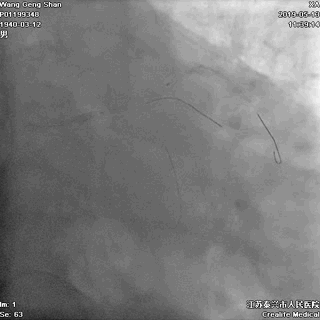

03 第一第二对角支保护

对角支导丝到位

左冠共计5根导丝

前降支近段支架植入后用非顺应性球囊高压扩张